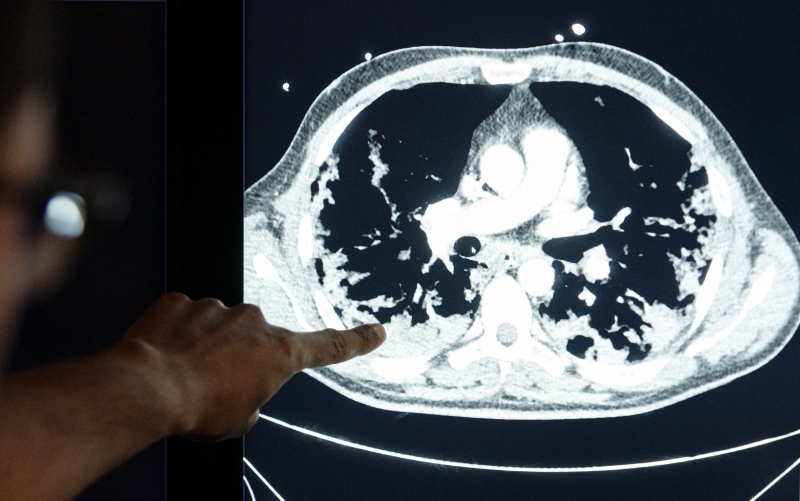

Abnormalities in the lungs of a COVID-19 patient. Photo: Thijs Rooimans

CT scans, which are part of standard care, will be analyzed using the latest artificial intelligence methods. Thirona will contribute by analyzing chest CT scans of participants for abnormalities with its CAD4COVID and LungQ software solutions.